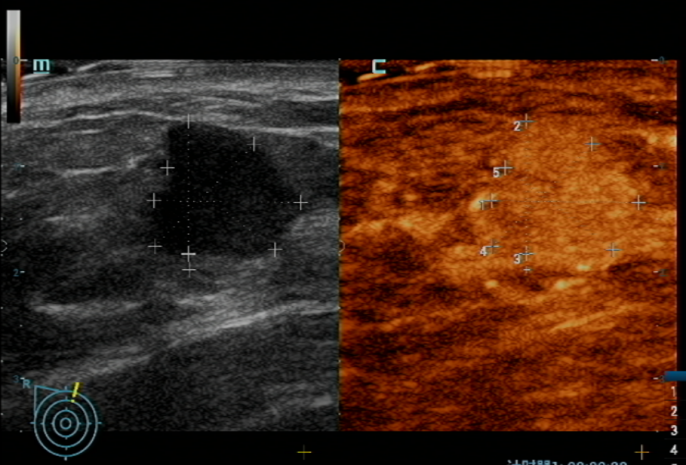

黄女士因“右侧乳房肿物”就诊于pilipili ,经影像学检查及穿刺活检,确诊为右侧乳腺浸润性癌。

在陈伦主任与pilipili 普外科团队的密切配合下,手术顺利开展。不同于传统乳腺癌根治术,此次采用的保乳手术仅切除肿瘤及周围少量组织,最大程度保留了乳房外形;同时通过前哨淋巴结活检术,精准检测腋窝淋巴结转移情况(仅1枚阳性),避免了全腋窝清扫可能导致的上肢水肿、活动受限等并发症。

术后病理证实:肿瘤完整切除,所有手术切缘(10个切缘)未见癌细胞残留,达到“根治性切除”标准。这种“精准微创”理念,不仅减少了手术创伤,更为患者后续康复和生活质量奠定了基础。